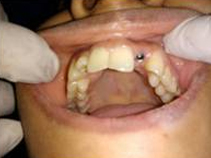

Pre Operation

Single Tooth Implant